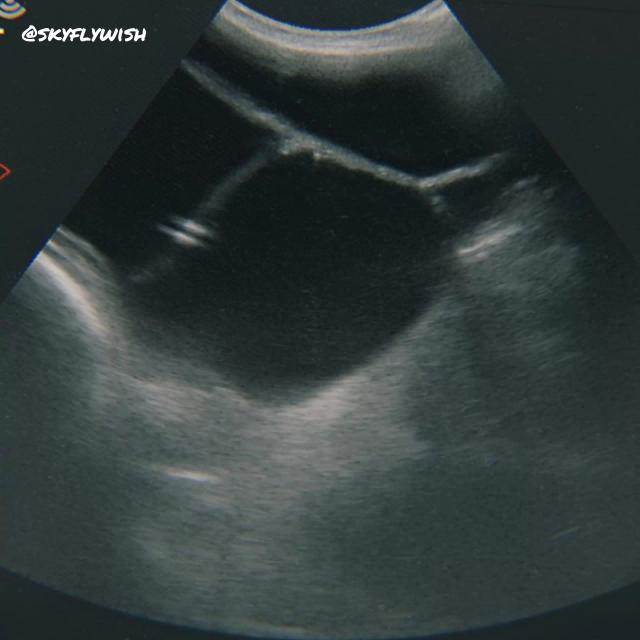

Даже анализы крови и мочи могут свидетельствовать о беременности. Единственный достоверный способ определения ложной беременность — УЗИ диагностика на 30-70 день после осеменения. Будет отмечаться жидкость в матке, но при этом плод отсутствует.